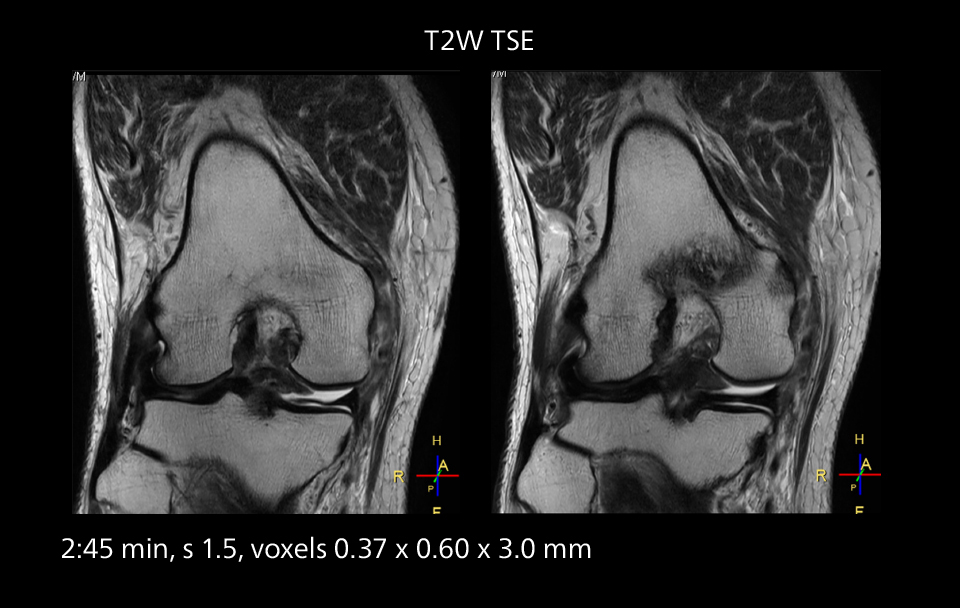

An example of increased imaging speed is in knee studies. “There is a definite scan time reduction for T2* mFFE and proton density TSE – both of these sequences benefit from much shorter repetition times,” he reports.

Images showing a posterior cruciate ligament (PCL) tear, a detached medial collateral ligament (MCL) on the tibial side and an intact anterior cruciate ligament (ACL). SmartPath to Elition X helped reduce scan time compared to previous imaging while maintaining resolution.

Overall, imaging time per sequence has been reduced since the Elition X upgrade. This can help reduce the risk of patient movement and the need for rescans.

“As our hospital has many elderly patients, we consider it important to obtain high-quality data in a short time,” Dr. Makuuchi says. “Shorter imaging times are also useful for accepting emergency patients, because faster emergency studies have a reduced impact on the daily examinations schedule. In emergency cases it is also important that high quality images are obtained in a short time.”